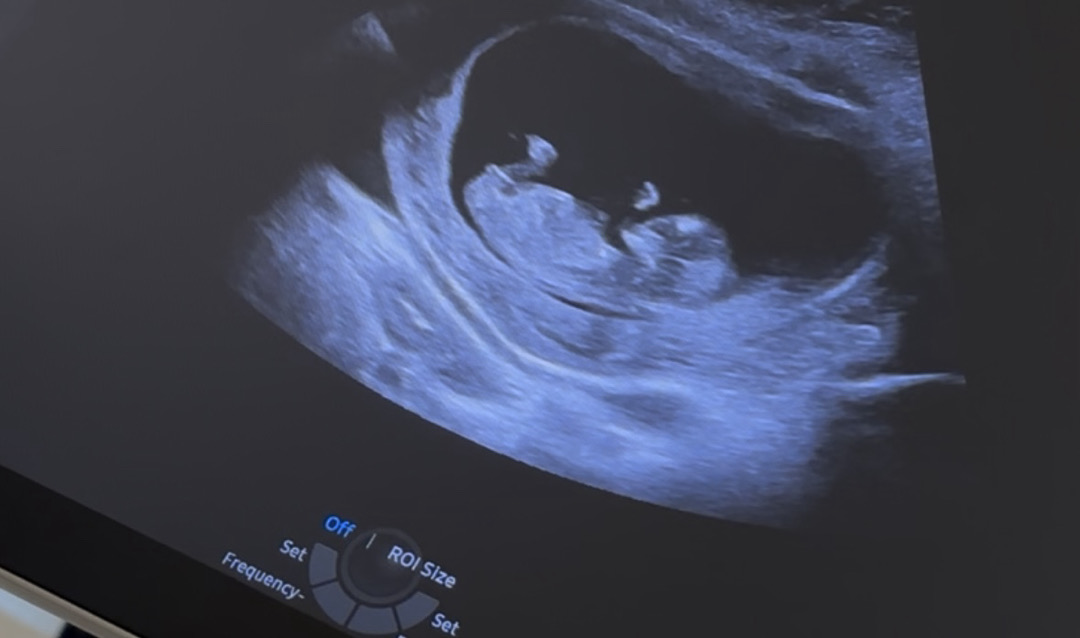

11주 5일차 각도법 봐주세요!

의사샘은 툭 튀어나와서 아들 같다고 하시는데 각도법으로 보면 딸 아닌가요..? 😅여러분들이 보시기엔 어때요??